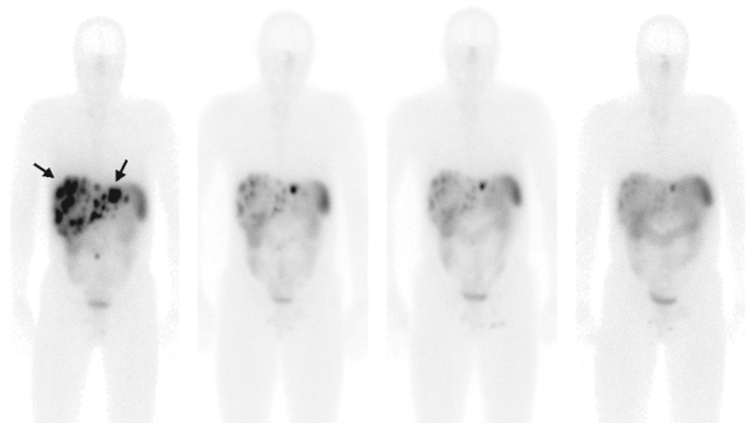

In het Erasmus MC bieden we in totaal drie soorten nucleaire therapie aan: lutetium-DOTATATE bij neuro-endocriene tumoren (NET), lutetium-PSMA bij prostaatkanker en radioactief jodium bij schildklierziektes. In sommige gevallen kunnen deze therapieën ook bij andere vormen van kanker worden toegepast.

Lutetium-DOTATATE (PRRT behandeling)

PRRT is de afkorting van Peptide Receptor Radionuclide Therapie. Deze therapie wordt gebruikt bij patiënten met NET en andere zeldzame vormen van kanker. Door het toedienen van het radioactief eiwit lutetium-DOTATATE bij de patiënt kunnen we tumoren met precisie behandelen. Dankzij deze behandeling verbetert in de meeste gevallen de kwaliteit van leven.